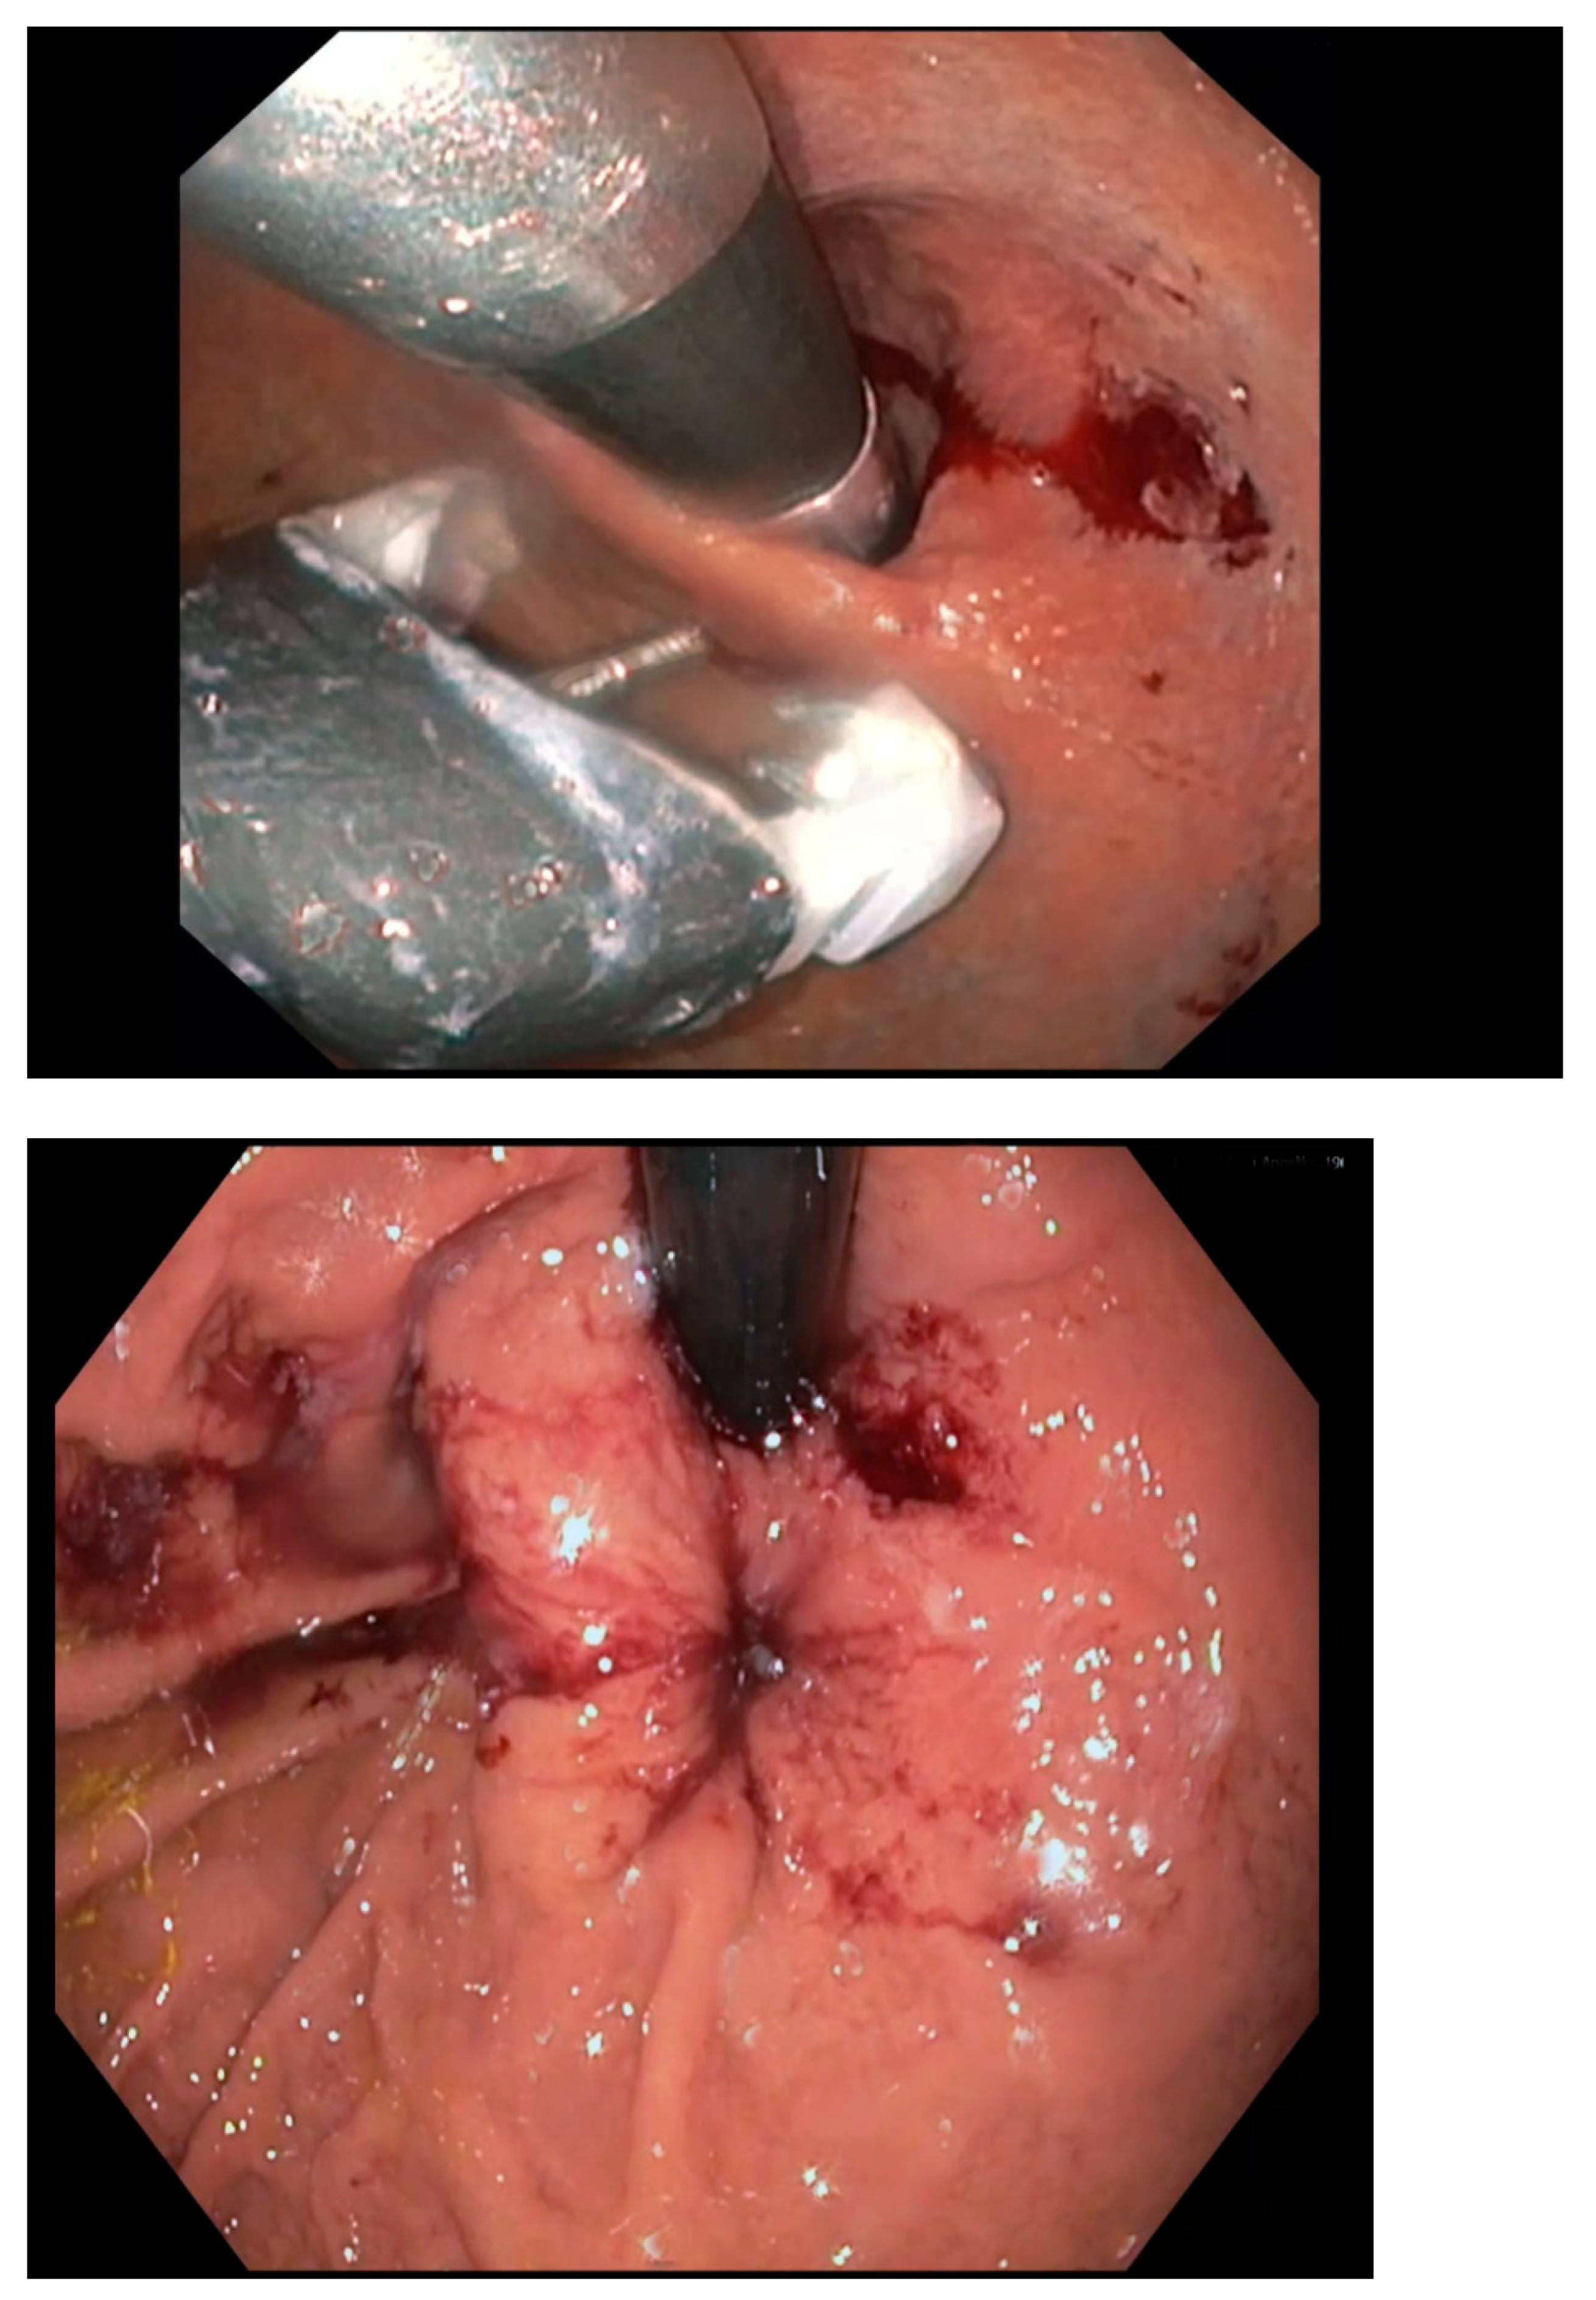

3. Transoral Incisionless Fundoplication (TIF) and Endoscopic Full Thickness Plication (EFTP)

Procedure Technique

- TIF: TIF is typically performed using the EsophyX (Endogastric Solutions, Merit Medical, UT, USA)) device, which uses fasteners to create folds in the stomach at the gastroesophageal junction. The goal is to reconstruct the valve-like function of the lower esophageal sphincter (LES) by creating a tighter anti-reflux barrier. TIF involves the creation of a 270–300° fundoplication, making it less invasive than traditional fundoplication surgery.

- EFTP: EFTP, by contrast, involves the use of transmural sutures, which go through the entire thickness of the stomach wall to secure the plications. This technique aims to improve LES function by placing full-thickness sutures at specific points to bolster the gastroesophageal junction’s barrier. Because it penetrates deeper layers of the tissue, EFTP can offer a more robust structural alteration. Endoscopic full-thickness plication is performed using the GERDx™ system (G-SURG GmbH, Seeon-Seebruck, Germany). The GERDx™ system is the advanced single use product of a company that has taken over the Plicator technology, after the Plicator device (Ethicon Endosurgery, Sommerville, NJ, USA) was taken off the market